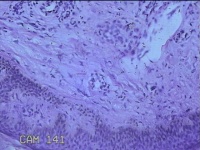

右侧头部息肉结节

性别

男

年龄

39岁

临床诊断

头皮良性肿瘤

一般病史

发现右侧头部息肉结节20余年。

标本名称

右侧头部息肉组织

大体所见

灰白暗红色组织1.2x1x0.8cm一块,表面带梭形皮肤1.2x0.8cm,皮下见结节1.2x0.9x0.3cm一个,切开结节呈实性,切面灰白暗红色,质软。